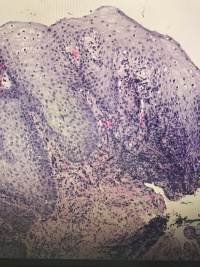

食道粘膜

腹痛,距门齿33cm处食管壁见0.4✖️0.5cm隆起

灰白组织一粒,直径0.1

鳞状上皮乳头状瘤性息肉,局部鳞状上皮轻度异型增生。

鳞状上皮下是幽门腺,胃粘膜异位

鳞上皮乳头上移,副基底层增生